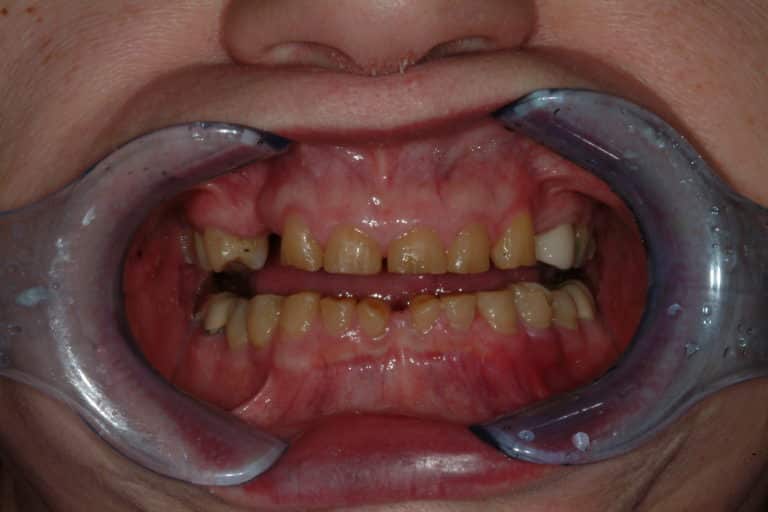

Before & After Gallery

Individual results may vary.